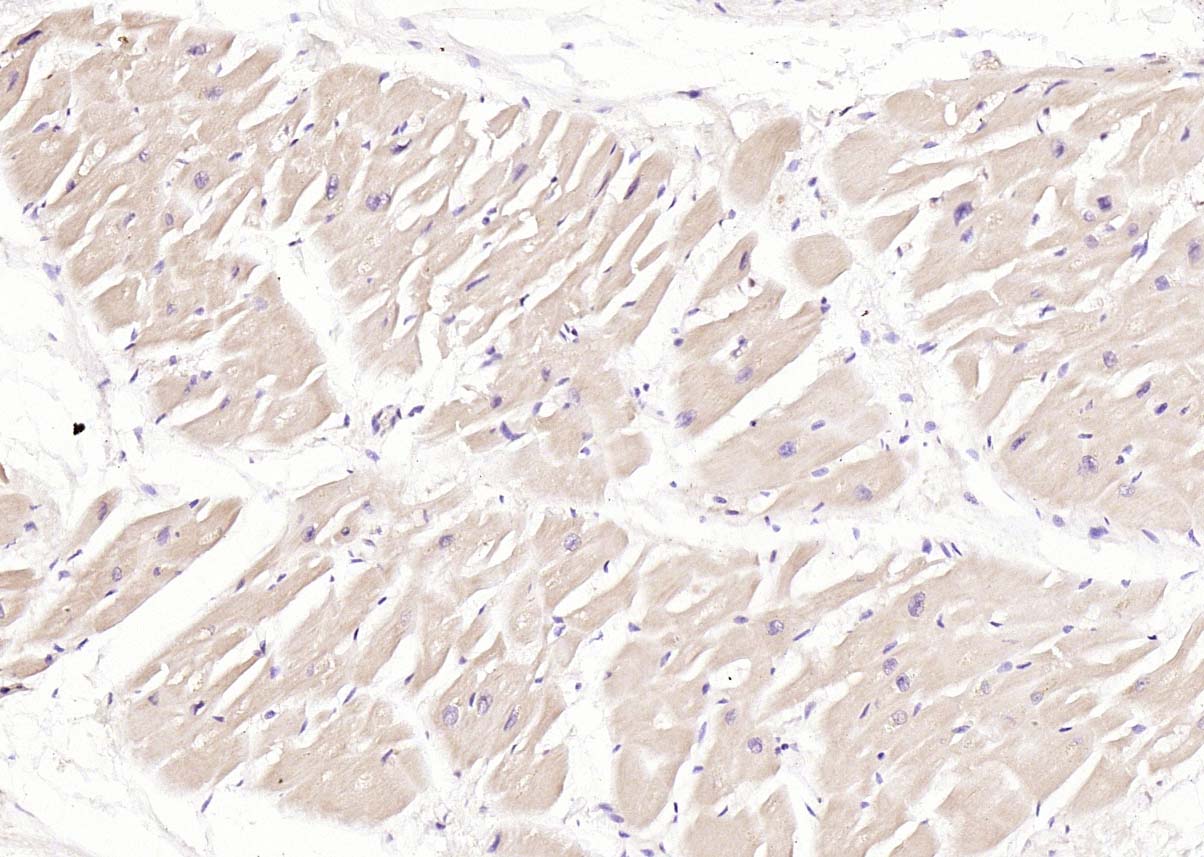

磷酸化结蛋白抗体-bs-5302R磷酸化结蛋白抗体-bs-5302R磷酸化结蛋白抗体-bs-5302R

IHC-PHuman1:100-500

IHC-FHuman1:100-500

IFHuman1:100-500